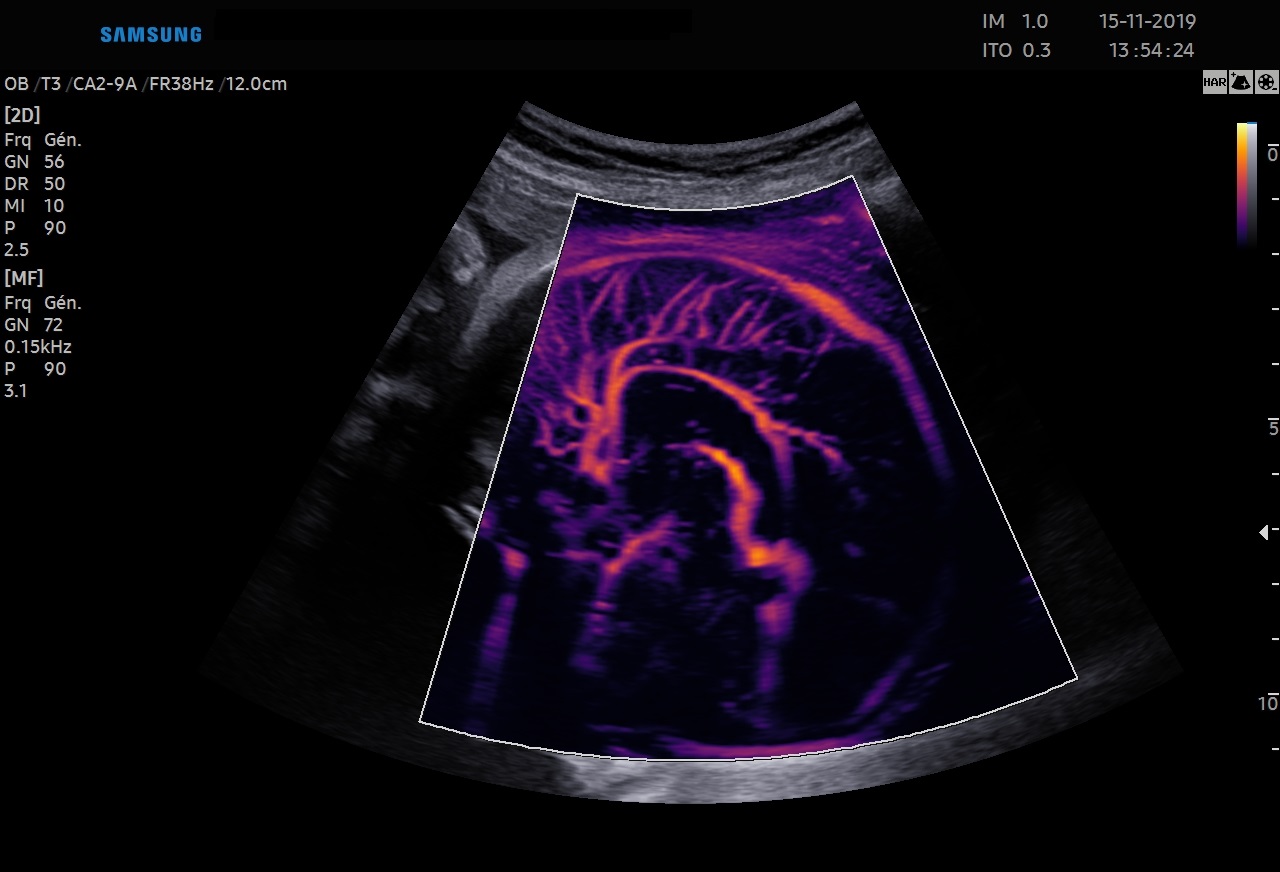

Les sondes de technologie S-Vue™ disposent d'une sensibilité accrue et d'une bande passante plus large que les sondes conventionnelles. Elles garantissent une résolution d’image optimale, même chez les patientes techniquement difficiles. De plus la petite taille et la légèreté de ces sondes améliorent les conditions d'examen au quotidien.

Abdomen, obstétrique, gynécologie

Abdomen, obstétrique, gynécologie, échographie de contraste

Obstétrique, gynécologie, abdomen, pédiatrie

Obstétrique, gynécologie, abdomen